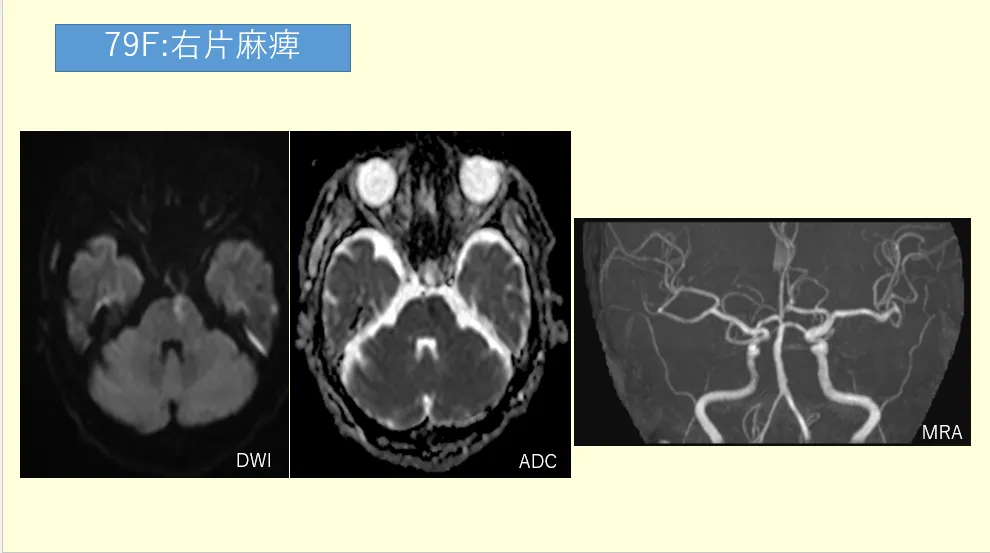

症例:78歳女性、右上下肢の脱力を主訴に来院。

左の基底核に拡散強調画像高信号域があります。梗塞巣は非常に小さく、ラクナ梗塞のように見えます。しかし、待ってください。スライスを上下に送ると、梗塞巣がずっと続いていきます…1枚、2枚…6枚にもわたって縦に長い。これは典型的なラクナ梗塞ではありません。続いて中大脳動脈(MCA)の閉塞を予測してMRAを立ち上げますが…結果は、異常なし。血管は驚くほどきれいです。心原性塞栓症を疑う既往歴もありません。

この症例は、まさにBAD(分子粥腫型脳梗塞)の典型例でした。本記事では、このBADの病態から画像所見、そして私たち放射線技師が現場で実践すべき鑑別診断のポイントまでを徹底解説していきます。